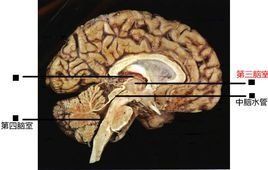

第三腦室

三腦室的前壁從上門絡氏孔伸廷到下方視交叉,它的主要組成部分是終板,向前與大腦縱裂相連,向後在三腦室的前壁和頂之間是前連合。三腦室的底是從前部視交叉到後部導水管,底的前半部是由間腦結構印與交叉池、灰結節、乳頭體和一個與腳間池相連的後穿通體相連的交叉隱窩和漏斗隱窩。後半部是由中腦結構形成。三腦室的後壁是從上方的上松果體隱窩到下方的導水管。